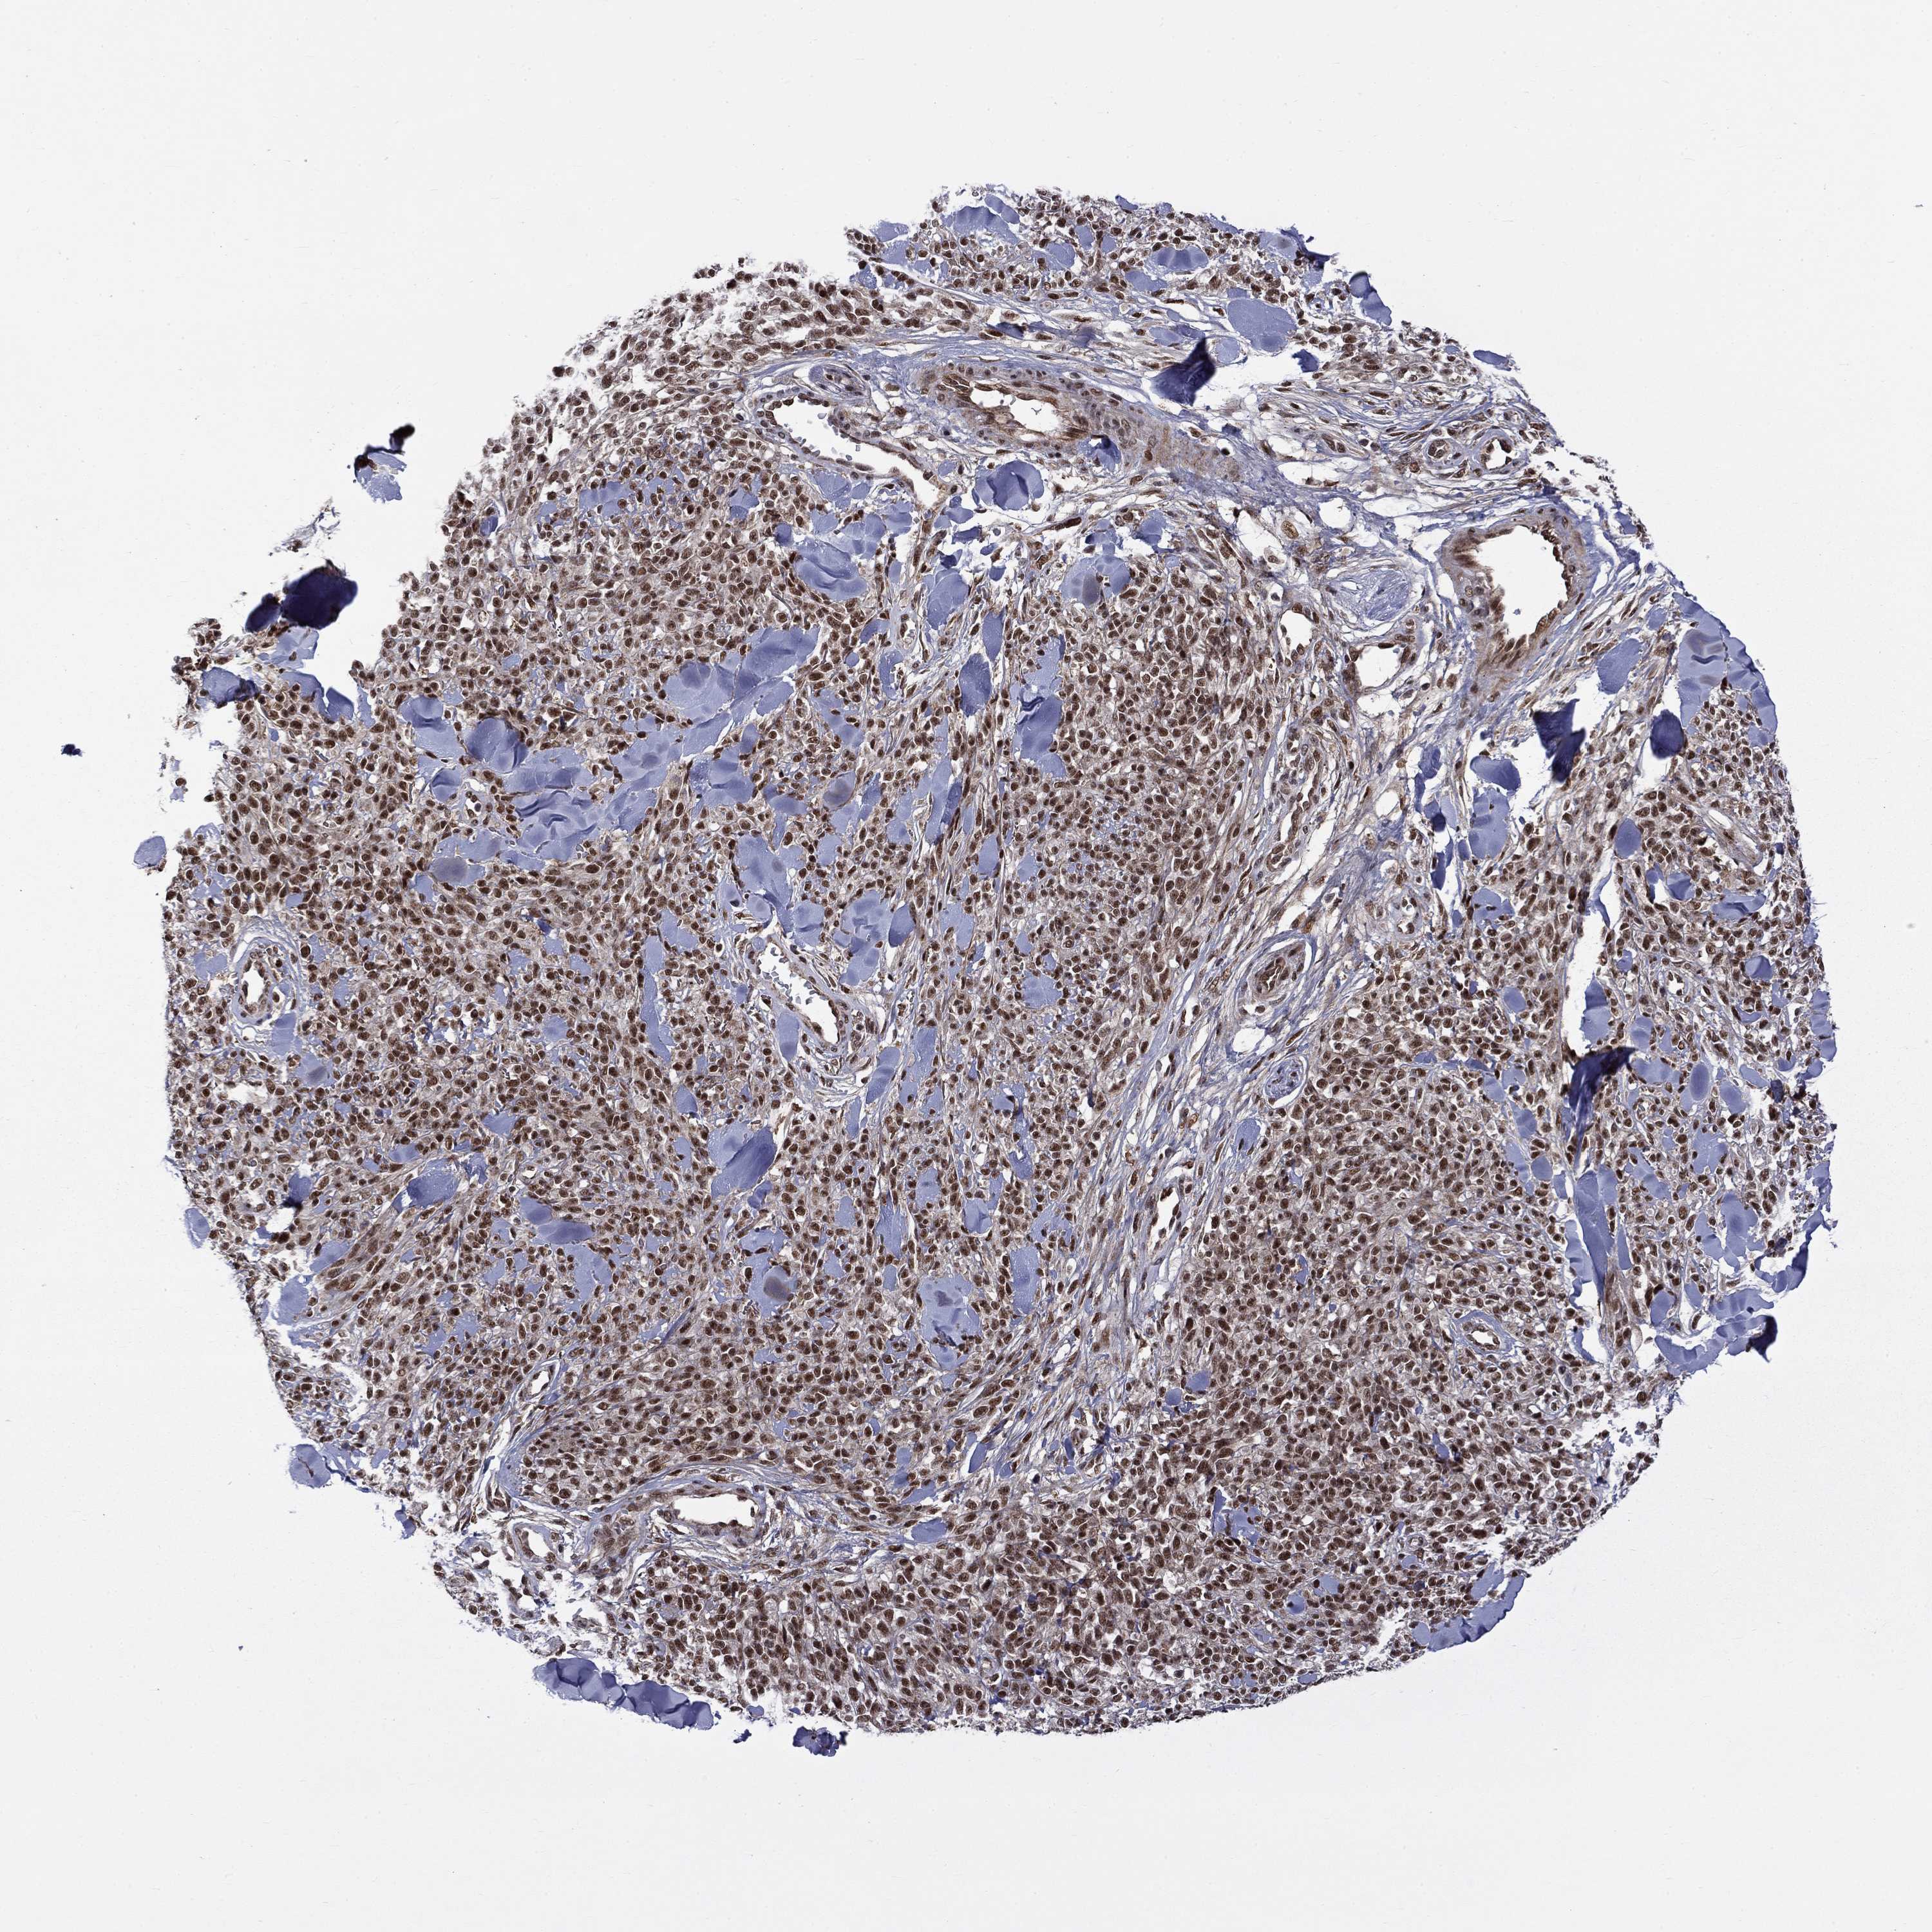

MELANOMA - Protein expressioni

A mouse-over function shows sample information and annotation data. Click on an image to view it in a full screen mode. Samples can be filtered based on level of antibody staining by selecting one or several of the following categories: high, medium, low and not detected. The assay and annotation is described here.

Note that samples used for immunohistochemistry by the Human Protein Atlas do not correspond to samples in the TCGA dataset.

Antibody stainingi

Antibody staining in the annotated cell types in the current human tissue is reported as not detected, low, medium, or high, based on conventional immunohistochemistry profiling in selected tissues. This score is based on the combination of the staining intensity and fraction of stained cells.

Each image is clickable and will lead to virtual microscopy that enables deeper exploration of all samples and also displays staining intensity scores, fraction scores and subcellular localization as well as patient and tissue information for each sample.

Antibody HPA046852

Antibody HPA077643

Staining

High

Medium

Low

Not detected

Intensity

Strong

Moderate

Weak

Negative

Quantity

>75%

75%-25%

<25%

None

Location

Nuclear

Cytoplasmic/membranous

Cytoplasmic/membranous,nuclear

Malignant melanoma, NOS

Malignant melanoma, Metastatic site